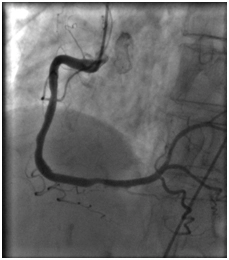

18.08.2011 выполнена селективная коронарная ангиография.

В процессе процедуры выявлено: ствол левой коронарной артерии обычно расположен. Передняя нисходящая артерия – в средней трети стеноз 80%.

Огибающая коронарная артерия без признаков стенозирующего атеросклероза.

Правая коронарная артерия – в средней трети стеноз 70%. Правый тип коронарного кровообращения.

Передняя межжелудочковая артерия